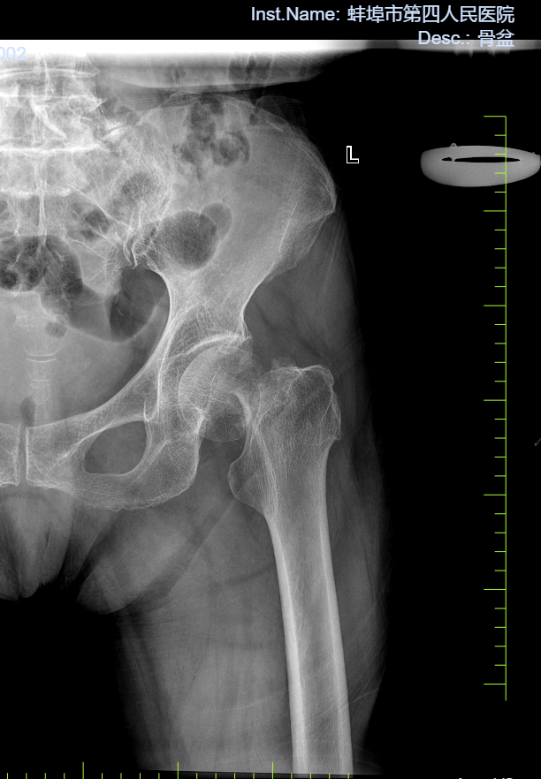

病例一:患者,男,71岁,因“左髋关节疼痛伴活动受限一周”入院。诊断:左侧股骨头无菌性坏死;行左侧全髋关节置换术,手术顺利,术后恢复良好,顺利出院。

左侧股骨头坏死 术前X线片 左侧股骨头坏死术后X线片